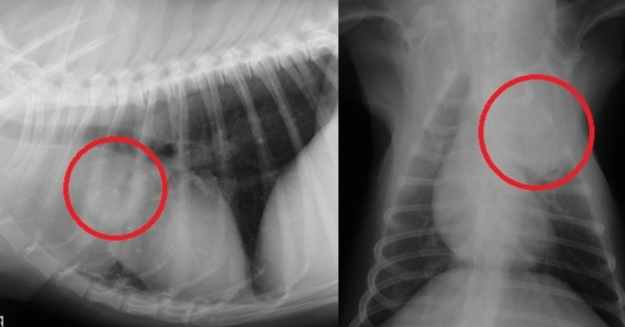

診斷過程通常需要多管齊下。獸醫可能會先聽診,然後建議做X光或超音波。X光是最基本的工具,可以看肺部的陰影變化。但如果腫瘤很小,X光可能看不出來,這時就需要進階檢查如CT掃描。

| 影像學檢查 | X光、超音波 | 查看肺部有無異常陰影 |

| 進階診斷 | CT掃描、活檢 | 確認腫瘤位置和類型 |